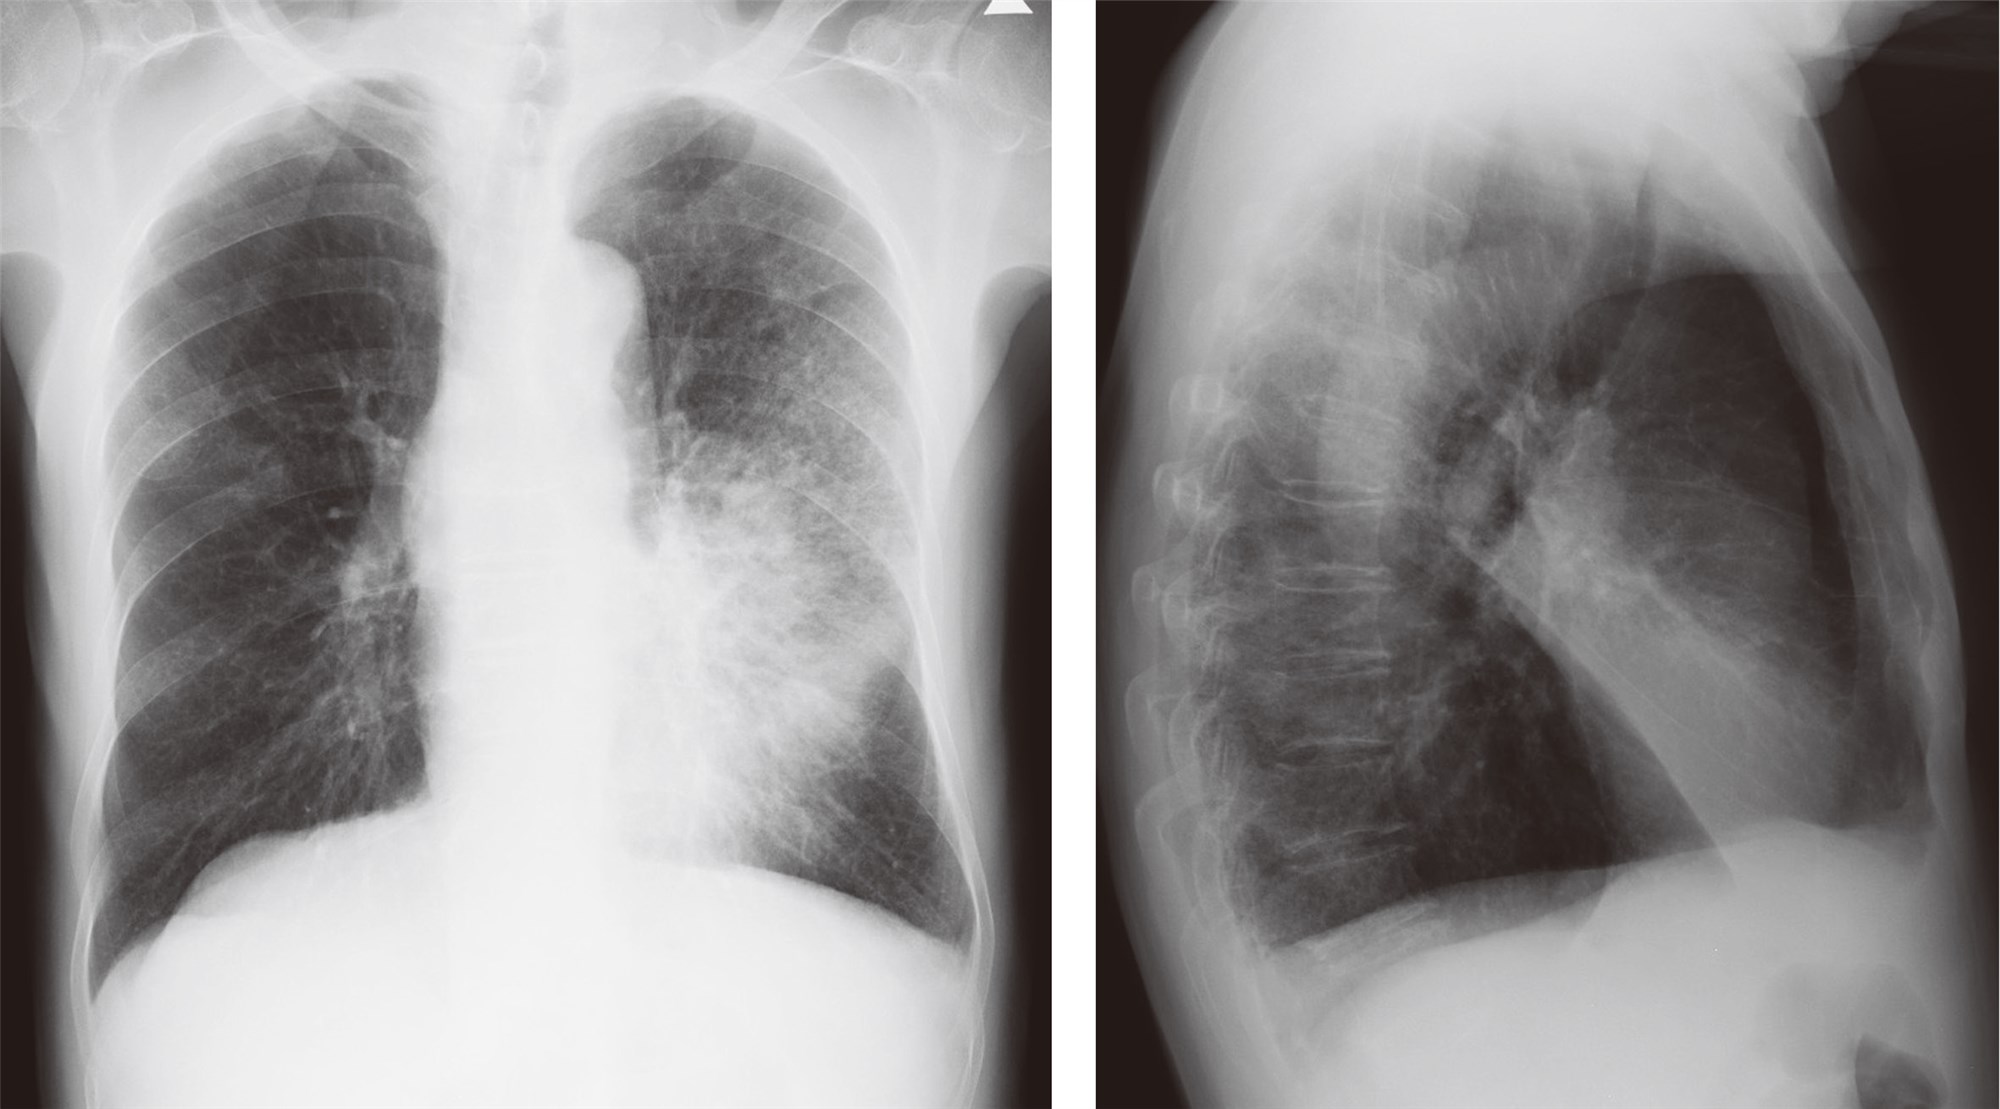

支气管肺炎ct影像表现,支气管肺炎x线表现

支气管肺炎x线表现

支气管肺炎胸片表现图

支气管肺炎影像图片

支气管肺炎ct图片

支气管肺炎胸片特点

支气管肺炎胸片

支气管肺炎胸片图解